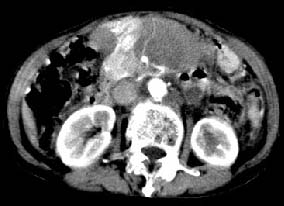

ct:肝胃之间、胰头后、腹主a周围,融合而成团块状影,包绕血管,胰腺前移后缘分界欠清,与肝胃分界清,肿块未见明显强化,肝右叶后段小囊肿。

诊断:淋巴瘤>转移瘤。

肝胃之间、胰头后、腹主a周围,融合而成团块状影,包绕血管,胰腺前移后缘分界欠清,与肝胃分界清,肿块未见明显强化,考虑淋巴瘤可能性大

胰腺受压前移,胰管扩张,应为腹膜后占位,病灶密度不均,有低密度坏死区,强化扫描强化不明显腹腔干动脉受侵,考虑腹膜后恶性占位

从发病部位(腹主动脉周围)及增强方式(均匀轻度强化、少量坏死)和病变形态(较大、多结节形)符合腹膜后淋巴瘤,建议颈部病变活检。

肝胃之间、肝十二指肠韧带,胰头后、腹主a周围,融合而成团块状影,包绕血管[腹腔干、肠系膜上动脉,腹主动脉],胰腺前移后缘分界欠清,与肝胃分界清,肿块未见明显强化,肝右叶后段小囊肿。

主动脉-胰腺间隙可见巨大分叶状软组织肿块影,包绕腹主动脉、腹腔干及其分支、腔静脉等大血管,增强呈无明显强化,临近脏器明显受压移位,增强示有分界。肝右叶可见局限性低密影,边缘清楚。

考虑腹膜后淋巴瘤。